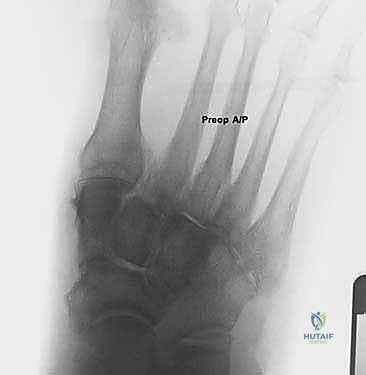

* الأشعة السينية (X-rays) مع تحمل الوزن: ضرورية لتقييم درجة انهيار القوس وزوايا العظام (مثل زاوية تالونافيكولار Meary's Angle).